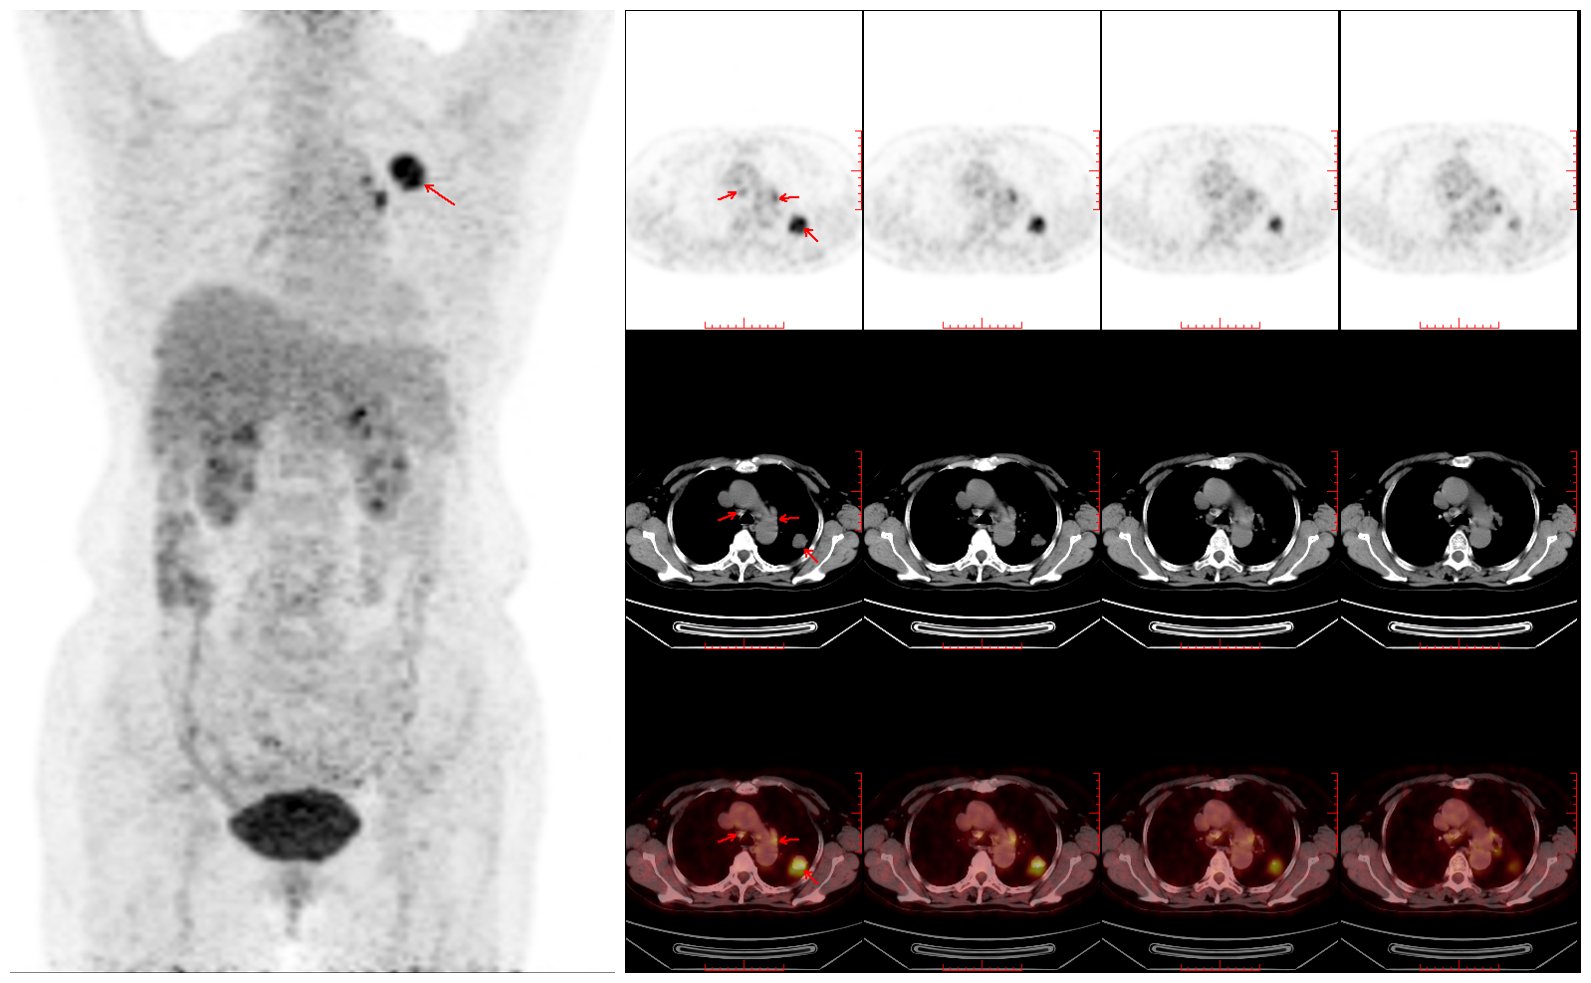

病例二 肿瘤分期 患者男,55岁。咳嗽、咳痰、咯血2+周,临床抗炎治疗无效,外院CT提示:左肺上叶尖后段结节状软组织密度影,大小约1.8cm×1.5cm,考虑肿瘤性病变;现行PET-CT了解全身情况,进行治疗前分期。全身PET-CT显像提示:左肺上叶恶性肿瘤伴纵隔、左肺门淋巴结转移。TNM分期:T1bN1M0。左肺上叶穿刺活检,病理示:左肺腺癌。